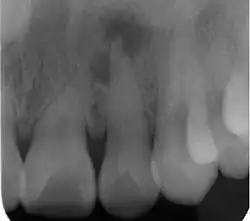

| Radiograph (X-ray) showing microdontia. Note also periapical lesion on the maxillary left lateral incisor. | |